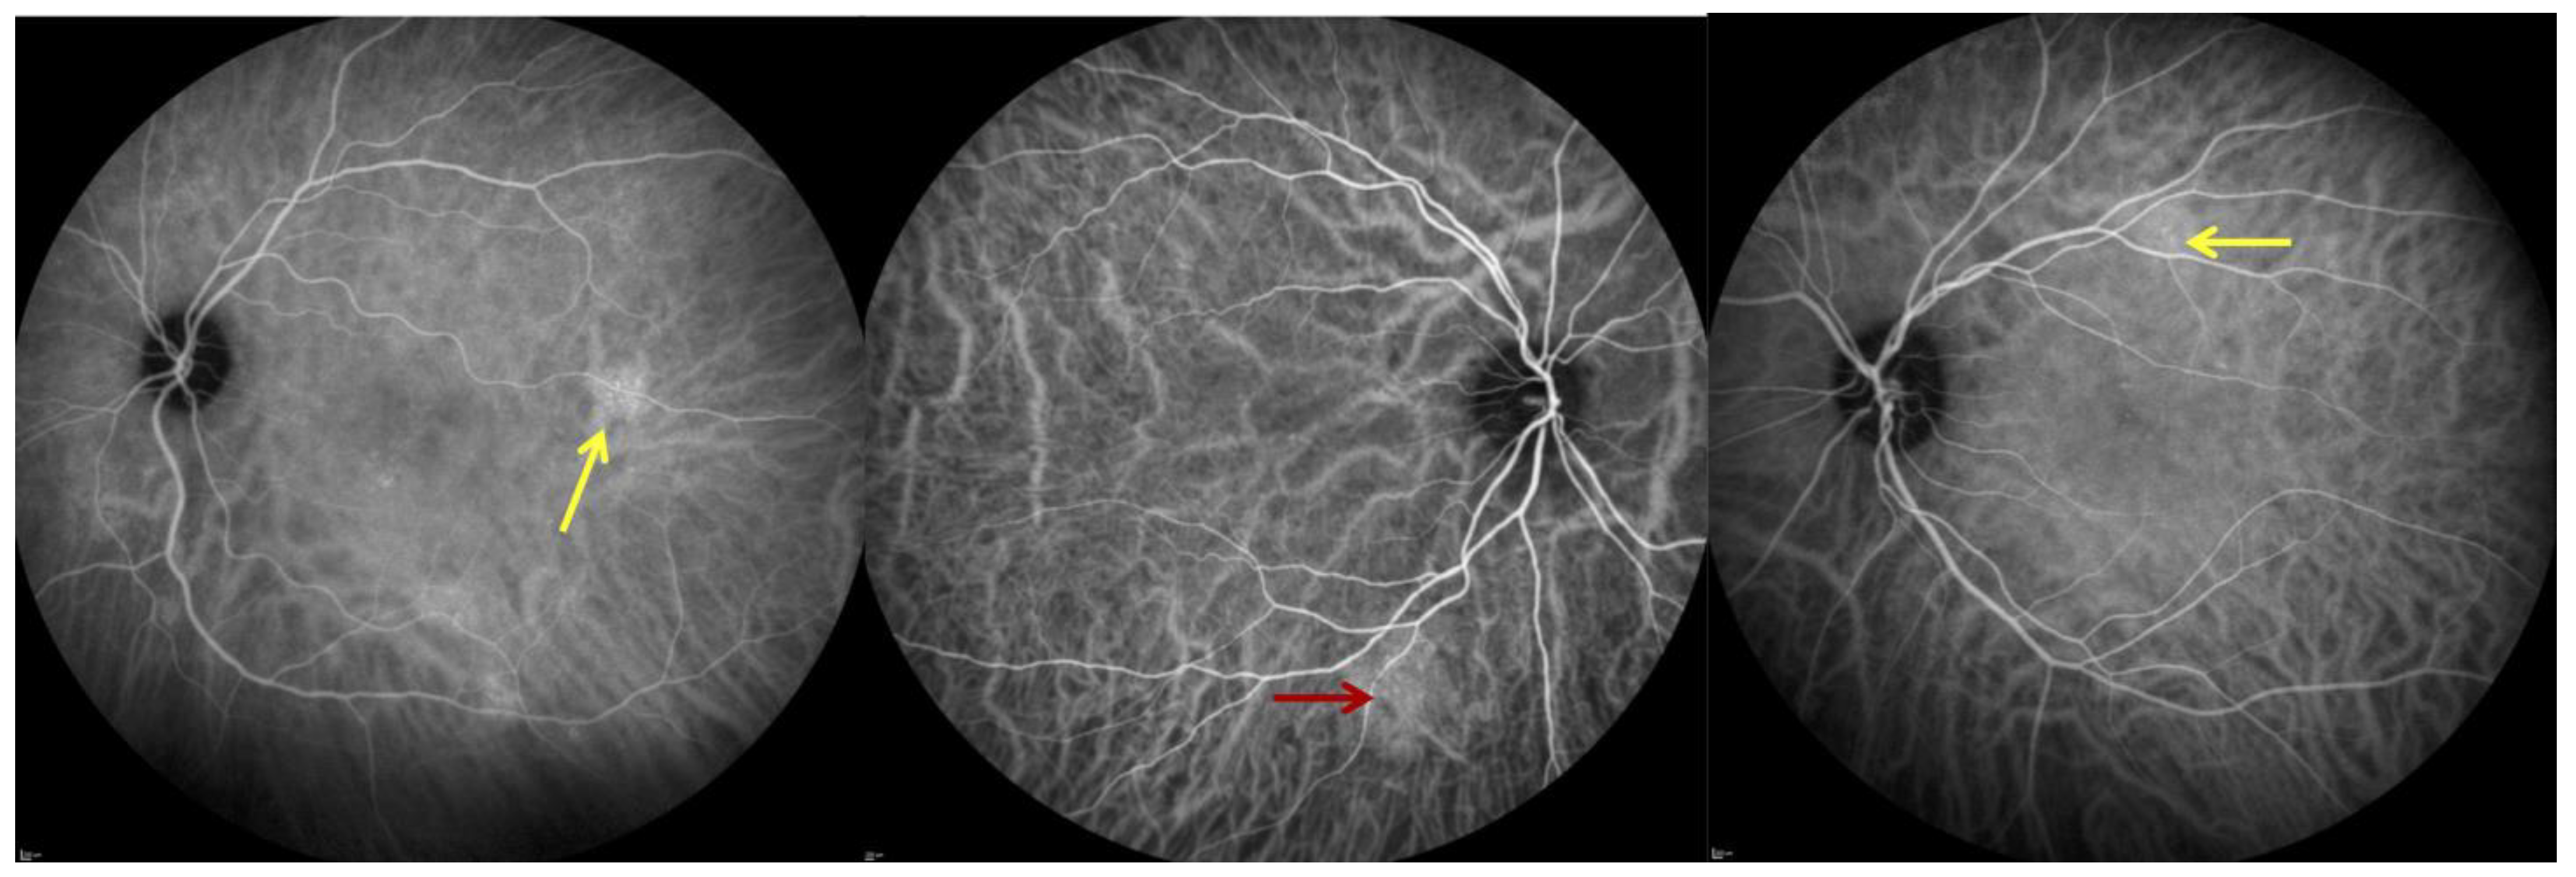

2.3. Optical Coherence Tomography (B-Scan) and OCT-A

2.4. Indocyanine Green Angiography (ICGA)

3.1. Study Population and Characteristics of Ocular Findings